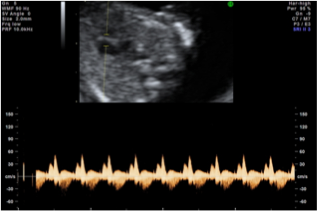

flusso sanguigno attraverso la valvola tricuspide

normale rigurgito tricuspidale

flusso sanguigno attraverso il dotto venoso

normale flusso invertito